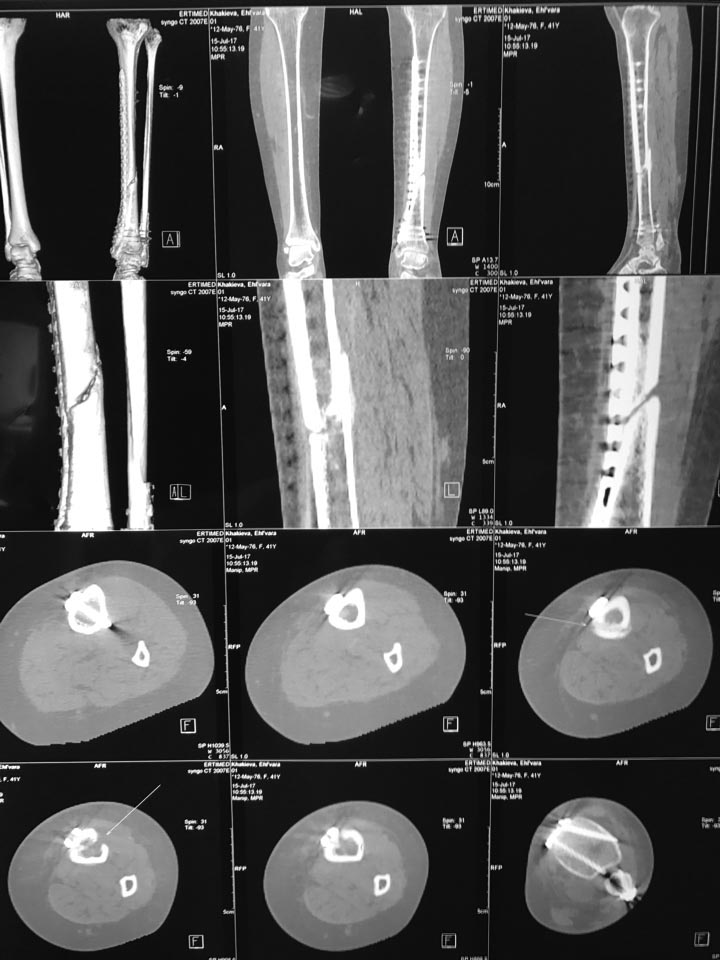

Уважаемые коллеги, нужна помощь в определении дальнейшей тактики лечения замедленно консолидирующегося перелома большеберцовой кости. Больная 37 лет, получила травму в феврале 2017 года. Закрытый косой перелом диафиза большеберцовой кости и нижней трети малоберцовой кости, со смещением отломков. Первичных снимков к сожалению не могу представить, перелом большеберцовой кости продолжался до дистального эпифиза. В феврале выполнен малоинвазивный остеосинтез большеберцовой кости пластиной с угловой стабильностью, остеосинтез малоберцовой кости 1\3 трубчатой пластиной. Послеоперационный период без осложнений. В настоящее время больная ходит с помощью костылей, рекомендации наступать не выполняет, хотя боли при осевой нагрузке не отмечает. Рекомендована ходьба с нагрузкой. Есть ли необходимость костной пластики? Показан ли реостеосинтез сейчас, или можно рассчитывать на сращение?

КТ выполнено, прилагаю фото.

Насчет остеосинтеза малоберцовой, выполнен остеосинтез косого перелома стягивающим винтом, с противоскользящей(опорной)функцией фиксирована 1/3 трубчатой пластиной.

Значит проблема в голове у пациентки. Ничего не меняется относительно данных кт. Ощущение,что есть сращение по задней поверхности. Надо заставить ппациенку опираться на ногу. Там и будет видно. Рентген оперировать не надо. Исходя из "психологического статуса" пациентки,даже если вдруг дойдете до реостеосинтеза,нет никаких гарантий, что она станет опираться на ногу. И да. Смущает отсутствие винтов в дистальном фрагменте малоберцовой кости.

Похоже, что есть сращение на ограниченном участке. По этим нескольким картинкам из КТ видно мало.

Больная сегодня явилась на консультацию, в настоящий момент ходит без дополнительной опоры, прихрамывая. Со слов больной ходит без костылей около 1 месяца. Отмечает умеренные боли в голеностопном суставе после нагрузки, боли в диафизе большеберцовой не отмечает. КТ выполнено 2 месяца назад, думаю сейчас уже не очень актуально, так как после него начала ходить с нагрузкой. Представленные рентгенограммы месячной давности. Рекомендована ходьба с нагрузкой, через 1 месяц рентген контроль..